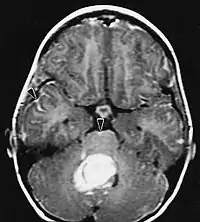

La tomodensitométrie (TDM) et L'imagerie par résonance magnétique (IRM) peuvent détecter efficacement une néoplasie dans le cerveau. L'IRM est plus sensible que la TDM pour identifier les lésions, mais présente des contre- indications pour les patients porteurs de stimulateurs cardiaques, de prothèses incompatibles, de clips métalliques et contre-indications. La TDM reste la méthode de choix pour détecter les calcifications au sein des lésions ou les érosions osseuses de la calotte ou de base du crâne. L'utilisation d' agents de contraste, iodés dans le cas du scanner et paramagnétiques (gadolinium) dans le cas de l'IRM, permet l'acquisition d'informations sur la vascularisation et l'intégrité de la barrière hémato-encéphalique, une meilleure définition de la tumeur tumorale par rapport à l' œdème environnant et à la génération d' hypothèses sur le degré de malignité. L'examen radiologique permet également d'évaluer les effets mécaniques et les modifications importantes des structures cérébrales résultant de la tumeur, telles que l' hydrocéphalie et les hernies, dont les effets peuvent être fatals. Enfin, en préparation à la chirurgie, ce diagnostic peut être utilisé pour déterminer la localisation de la lésion ou l'infiltration de la tumeur dans des zones vitales du cerveau. À cette fin, l'IRM est plus efficace que la tomodensitométrie car elle peut fournir des images en trois dimensions.

Les outils d'imagerie radiologique diagnostique mettent en évidence la modification du tissu néoplasique par rapport au parenchyme cérébral normal (par le biais de modifications de la densité tissulaire imagée électroniquement en TDM et de l'intensité du signal en IRM). Comme la plupart des tissus pathologiques, les tumeurs sont également reconnaissables par une accumulation accrue d'eau intracellulaire. Dans la tomodensitométrie, ils apparaissent hypodenses, c'est-à-dire de moindre densité que le parenchyme cérébral, dans la tomographie par résonance magnétique nucléaire avec relaxation spin-réseau hypointense et en relaxation spin-spin ainsi que l' hypersignal en pondération protonique (PD).

Dans le tissu tumoral, en général, la plus grande proportion d'amélioration du contraste est due à la barrière hémato-tumorale particulière qui permet le passage de l'iode (CT) et du gadolinium (IRM) dans l'espace interstitiel extravasculaire intratumoral. Cela augmente le signal (densité ou intensité) de la tumeur. Cependant, des précautions doivent être prises pour s'assurer que l'amélioration du contraste ne différencie pas définitivement la néoplasie de l'œdème péri-lésionnel. En fait, la découverte anatomo-pathologique dans le tissu tumoral infiltrant malin du gliome, comme dans le glioblastome et l'astrocytome anaplasique, montre également au-delà de l'œdème vasogénique causé par la destruction de la barrière hémato-encéphalique par la tumeur. Cette dernière condition clinique est difficilement détectable par imagerie diagnostique.

La tomodensitométrie du cerveau montre généralement une masse tissulaire qui peut être améliorée par l'un ou l'autre contraste. Au scanner, les gliomes de bas grade apparaissent généralement isodenses au parenchyme normal et peuvent donc ne pas présenter de rehaussement de contraste. De même, les lésions de la fosse crânienne postérieure sont difficiles à identifier au scanner. Par conséquent, les seuls résultats d'une telle tomographie ne sont pas toujours suffisants à des fins diagnostiques. Dans les cas douteux, l'utilisation de l'imagerie par résonance magnétique plus sensible est indispensable.

Sur-L'IRM montre une tumeur intracrânienne comme une lésion massive qui peut devenir plus luminescente après utilisation du produit de contraste. Cependant, il y a toujours une anomalie de signal dans -L'imagerie par résonance magnétique, qui indique la présence d'une néoplasie ou d'un œdème vasogénique. Habituellement, une luminescence accrue (amélioration du contraste) indique une tumeur d'un grade supérieur de malignité. Un anneau de contraste est caractéristique du glioblastome, avec la partie luminescente correspondant à la partie vitale de la tumeur maligne, et la plus foncée - zone hypointense correspondant à une nécrose tissulaire.